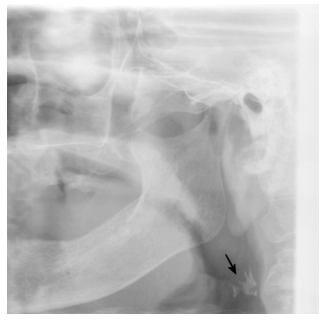

59. 附圖中箭頭所指之鈣化最可能是:

(A) Carotid artery calcification (B) Phlebolith (C) Sialolith (D) Lymph nodes